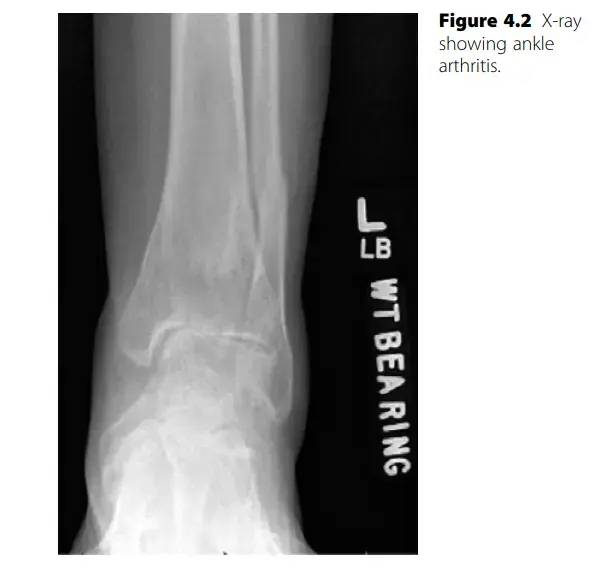

3. الأشعة السينية (X-rays): تُعد الأشعة السينية هي الاختبار التصويري الأول والأكثر أهمية. تظهر الأشعة تضييق المسافة المفصلية (مؤشراً على تآكل الغضروف)، وجود نتوءات عظمية، وتغيرات في بنية العظام. يمكن أن تُظهر الأشعة أيضاً علامات على كسور قديمة أو تشوهات.

الأشعة السينية مساحة مفصلية واسعة، عظام سليمة مساحة مفصلية ضيقة، تآكل العظام، نتوءات عظمية